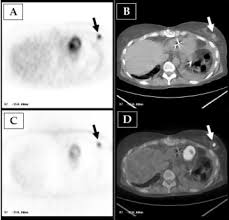

Learn more about how the test is done and what. If you have a pet scan: Mammogram and breast us may sometimes be better. Ct scans are most often done as an outpatient procedure. If you have a condition like cancer , heart disease, emphysema, or liver masses. Learn how this test works, as well as its benefits and risks. Ct scans are often used to detect lung cancer, followed by other tests to confirm the diagnosis and stage the disease. Breast cancer with mixed bone metastases (top ctscan, centre spect scan, bottom fused spect/ct images).

Bone scans, positron emission tomography (pet), and computed tomography (ct) all continue to be employed alone or in combination for the detection of breast cancers suspected to have spread. Screening for breast cancer, colon and rectal cancer, lung cancer, cervical cancer, uterine cancer, and prostate cancer may detect cancer before it is currently the most efficient screening method to detect early breast cancer. Pet/ct scan combinations detect cancer in its earliest stages, when changes are happening at the cellular level. It takes pictures from different angles. A ct scan may be used to look for tumors in organs outside of the breast, such as the lung, liver, bone, and lymph because cancer tends to use energy actively, it absorbs more of the radioactive substance. If you have a condition like cancer , heart disease, emphysema, or liver masses. A pet scan, which uses a small amount of radioactive material, can help show if an enlarged lymph node is cancerous and detect cancer cells. What cancers can be detected by ct scans? Mammogram and breast us may sometimes be better. Ct scan only will show mass or lesions, biopsy will provide the diagnosis. Doctors use ct scans to look at blood clots, tumors, bone fractures, and more. A scanner then detects this substance to produce. A chest computed tomography (ct) scan is an imaging test that takes detailed pictures of the lungs and the inside of the chest.